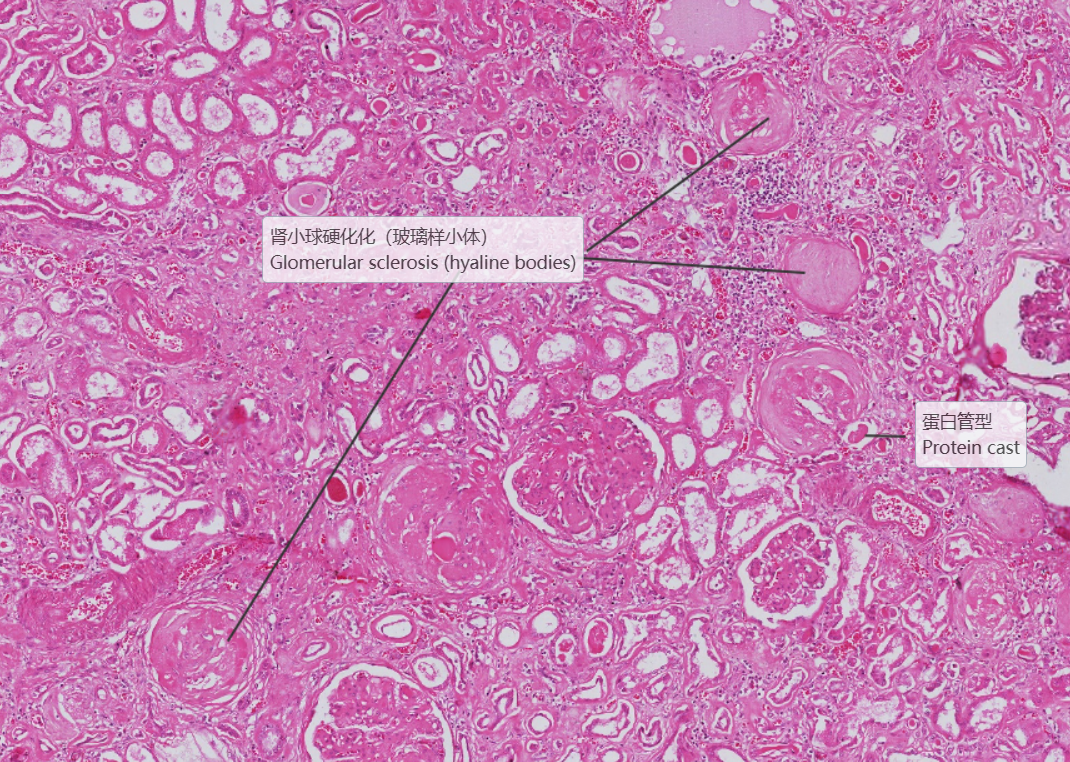

糖尿病肾病:1.大部分肾小球系膜区大量基质增多,较多形成结节状扩大,少数细胞靠结节边缘排列, 形成典型的K-W结节。部分节段有系膜细胞轻度增生, 基膜增厚。2.少数小球伴有球囊壁纤维化。 少部分肾小球硬化(玻璃样小体)。3.肾小管较多灶性萎缩,部分肾小管扩张,管腔内有蛋白管型。4.间质广泛纤维化,伴大量炎症细胞浸润(淋巴细胞、浆细胞)。许多肾小球入球细动脉壁增厚玻变, 间质肌性小动脉内膜增厚纤维化。

2.肾小球多个W-K结节形成

3.肾小球硬化

4.肾小管扩张